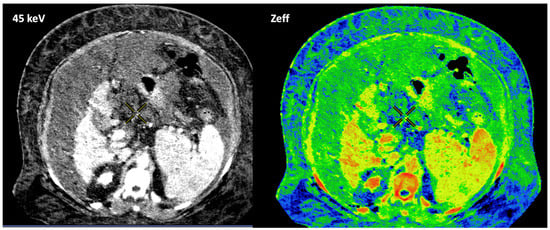

Figure 12. Breast 120 kVp-like (a) and color-coded iodine map (b) images. Breast lesion detection. Multicentric left breast invasive ductal carcinoma can easily be detected based on iodine uptake (dotted circle) compared to the 120 kVp-like image, where the diagnosis is challenging. - Currently, there is not a widely reported use of DECT in clinical management of prostate cancer. However, DECT imaging may facilitate the depiction of focal areas of increased enhancement in the periphery of the prostate in contrast-enhanced CT that may represent a clinically significant cancer and deserve further workup [42] (Figure 13).

Figure 13. Prostate cancer (PCa) diagnosis. Incidental detection of a focal area of increased enhancement in the periphery of the prostate in contrast-enhanced CT may represent a clinically significant cancer (arrows) deserving of further workup. DECT imaging-based data such as a monoenergetic image at low energy values (e.g., 45 keV) and color-coded iodine map facilitate its detection. Note the difference between the spectral curve of the tumor (yellow curve, 1) and the normal parenchyma (blue curve, 2). Biopsy evidenced a prostate cancer having a Gleason score of 3 + 4. - LN characterization is challenging in oncologic imaging. Apart from morphologic criteria, different DECT parameters have been used, including iodine concentration, fat fraction, and similarity to the primary tumor [41,43]. Sauter et al. [44] evaluated standard values for of iodine concentration for healthy LNs in different anatomic areas that could be used to differentiate between healthy and pathological LNs. Recent studies have suggested lower iodine concentration in metastatic LNs compared to benign LNs [45]. However, the value of DECT imaging in differentiating malignant from non-malignant LNs seems to be limited and depends on the tumor type and technical features such as the protocols used for acquisition and contrast injection (Figure 14).